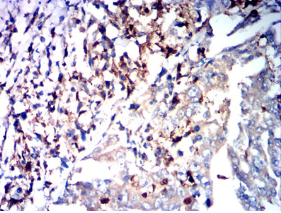

PTH Mouse Monoclonal antibody[8C5H9]

Immunogen:    Purified recombinant fragment of human PTH (AA: 32-115) expressed in E. Coli.

IHC    1/200 - 1/1000